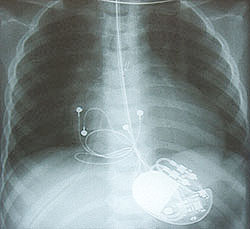

Eine plötzliche Ohnmacht kann diese Veränderung die man im EKG (Elektrokardiogramm) ablesen kann,

aufzeigen. Eine Schrittmacheroperation korrigiert diesen Zustand. Dabei werden Elektroden in

die Herzhöhlen geschoben und mit dem „Schrittmacher“ verbunden, der ein Computer mit Batterie ist.